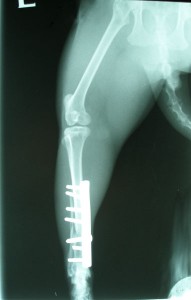

Po operaci obou kostí